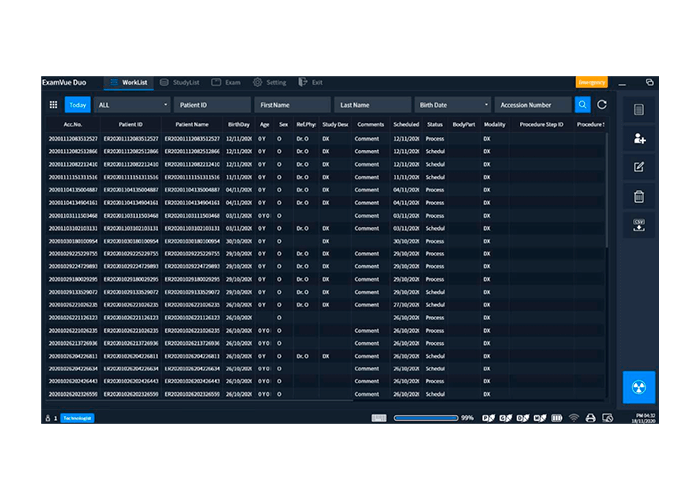

Interfase Digital

ExamVue DTS Suite

Una Extensión del Ecosistema de ExamVue Duo

El software exclusivo para StriXion™ combina imágenes de rayos X en tiempo real (fluoroscópicas), rayos X convencionales y tomografía en una única solución. Utilizando la misma plataforma intuitiva y avanzada de ExamVue™ Duo, el software de StriXion™ permite un control completo sobre la adquisición de imágenes, la técnica utilizada y el proceso de diagnóstico.